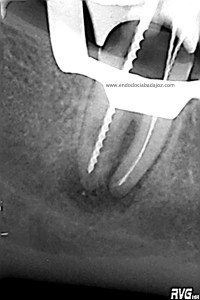

Hemos llamado a revisión a la paciente en varias ocasiones ( 6 meses y 9 meses)

(revision a los 6 meses) (revisión a los 9 meses)

Como podemos observar, la lesión periapical ha regenarado: